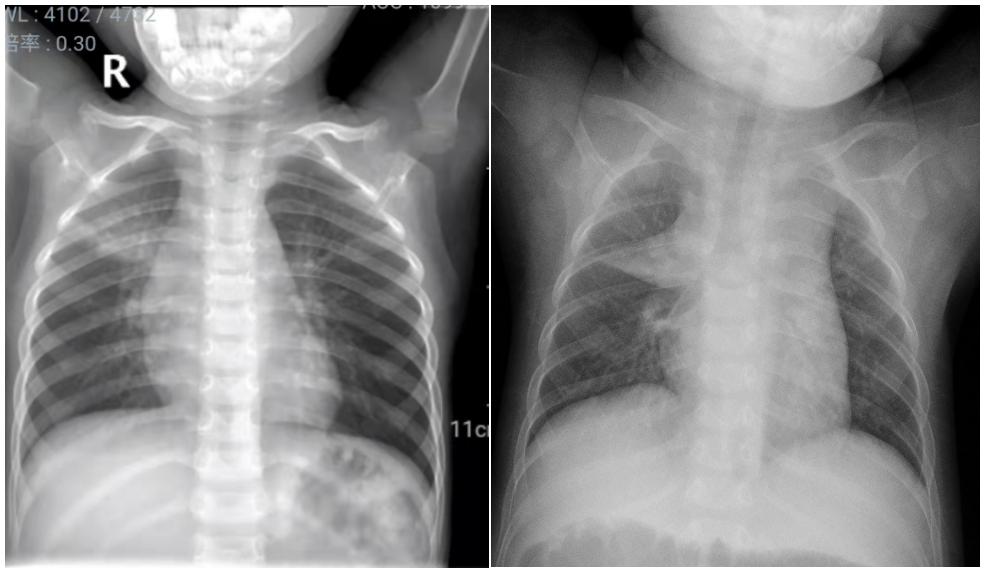

近日,有几个呼吸系统疾病患儿的胸片,引起年轻的规培医师的疑问,如下图1、图2所示:

图1示:左侧胸片为右上肺炎征象;右侧胸片示胸腺影

图2示:左侧胸片为右上肺炎征象;右侧胸片示胸腺影

以上2组图片,你能区分哪张是肺炎患儿,哪张是正常胸腺影像吗?

图1、图2左图均显示右上肺可见大片状、云雾状模糊影,结合患儿临床表现如发热、咳嗽、听诊可闻及呼吸音减低,出现痰鸣音或细湿性啰音等可明确为肺炎征象;

图1右图显示单侧致密均匀三角形,内缘与纵膈相连,下缘位于水平叶裂位置,边缘均清晰锐利。图2右图显示致密均匀,内缘位于纵膈内,外缘自内上斜向外下延伸,虽然因肺门影影响而似乎边缘不够清晰,放射科医师可通过不同层次的显现,可明确观察到系同一组织的征象。

2组胸片表现极为相似,正所谓:两兔傍地走,安能辨我是雌雄?这就要我们临床工作者,尤其是影像学科的年轻医师了解和熟悉婴幼儿胸腺的影像表现了。